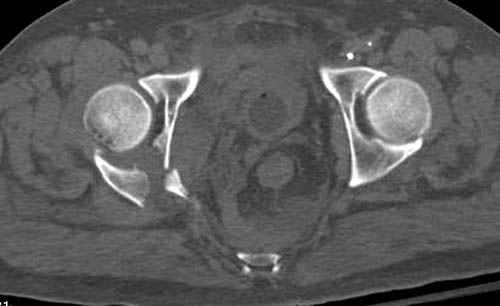

Наш недавний случай перкутанной фиксации "методом

Сиэтла" спицами 2.8 мм с резьбой на конце.

Второй случай, для лечения перелома проксимального

плеча применили пластину "Hand Innovation"

http://www.handinnovations.com/pdf/S3_technique.pdf

Пластина имеет преимущества перед другими "Locking

Implants", потому что пластину можно уложить намного ниже чем другие пластины и имеется возможности проведения шурупов под 130 градусным углом, таким образом можно уменьшить операционный разрез в проксимальной части.

Прооперирован вчера на 13 день после поступления.

Больному 41 и из-за гемодинамической нестабильности в течение первых 7 дней был в реанимации под интубационной седацией.

Кроме перелома плеча у больного старый дистракционный перелом T12-L1 оперированный когда-то и кем-то, открытый перелом костей предплечья, который был прооперирован в ночь поступления, после I&D (хирургической обработки). Из-за разрыва селезенки при поступлении травма хирургами произведено удаление.

Дополнительно имеется перелом ацетабулума: задняя

колонна с полупоперечным переломом, и переломы костей лица.

На седьмой день зафиксирован перелом ацетабулума через задний доступ. Перед операцией для профилактики DVT, IVC фильтер, также получает Lovenox.

Извиняюсь за качества снимков, обычный больной в 300 фунтов, портативным ренген аппаратом не пробить.